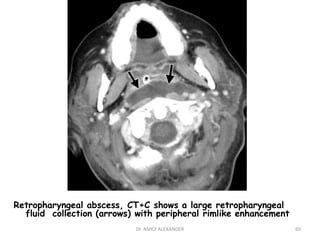

Retropharyngeal abscess, CT+C shows a large retropharyngeal

fluid collection (arrows) with peripheral rimlike enhancement

60

• 60.

Retropharyngeal abscess, CT+Cshows a large retropharyngeal fluid collection (arrows) with peripheral rimlike enhancement 60 Dr. ASHLY ALEXANDER